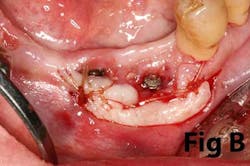

Case No. 1

Case No. 2